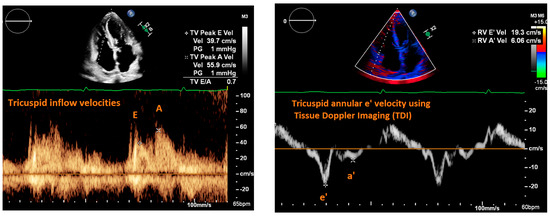

| Fletcher et al., 2020 [9] | Systematic review | Tricuspid inflow velocities | Patients with valvular disease, altered RV systolic function, recent cardiac surgery, acute heart failure, heart transplant, pulmonary hypertension, atrial fibrillation | Strength of correlation between E/e’ and RAP | 17 articles | Consistent positive correlation between E/e’ and RAP in patients with reduced RV systolic function; equivocal support correlating E/e’ and RAP in heart failure patients. |

| Cardiac Ultrasound | ||||

| Mitral E/e’ ratio estimated from the E wave velocity of the mitral inflow Doppler envelope and the tissue Doppler e’ wave velocity at the mitral annulus (septal and/or lateral) | E/e’ ≤ 14 |

|

| |